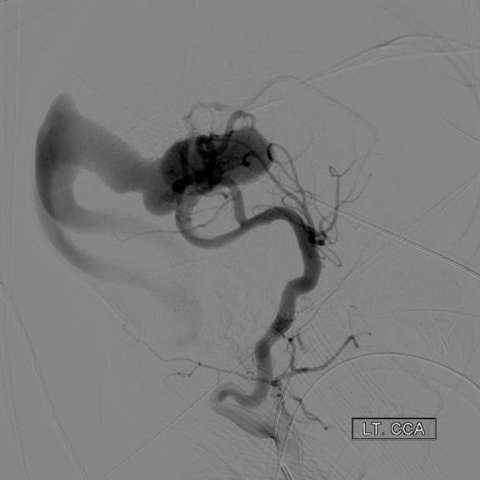

- Cranial Angiography - cranial angiography is usually performed in the setting of endovascular treatment

Endovascular embolization is the preferred method of treatment. In an embolization, the abnormal blood vessels are intentionally closed with soft platinum coils or liquid embolic agents, which reduce the abnormal blood flow to the vein of Galen. Sometimes, several procedures are required over a period of several months.